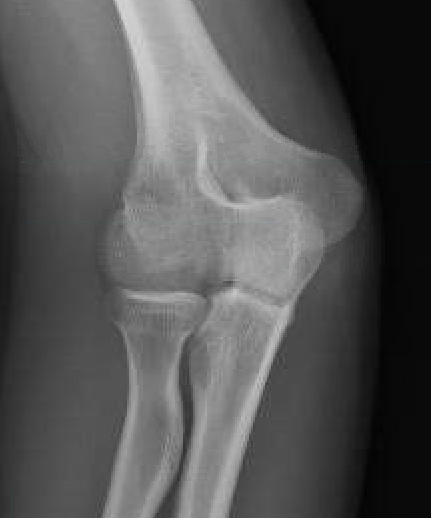

Bryan & Morrey Classification

Type I Type II

Large osseous fracture of the capitellum

Articular cartilage injury with little bone

Hanh Steinthal fracture

Kocher Lorenz fracture

Concomitant injuries

Radial head

Watts et al JBJS Br 2007

- 79 capitellar fractures

- 24% had a radial head fracture as well

LCL

Dubberley et al JBJS Am 2006

- 27 capitellum fractures treated with surgery

- 41% had associated LCL injuries

- 7/11 LCL injuries were avulsion fractures of the lateral epicondyle

Capitellum fracture with radial head fracture

Capitellum fracture with radial head dislocation due to LCL injury